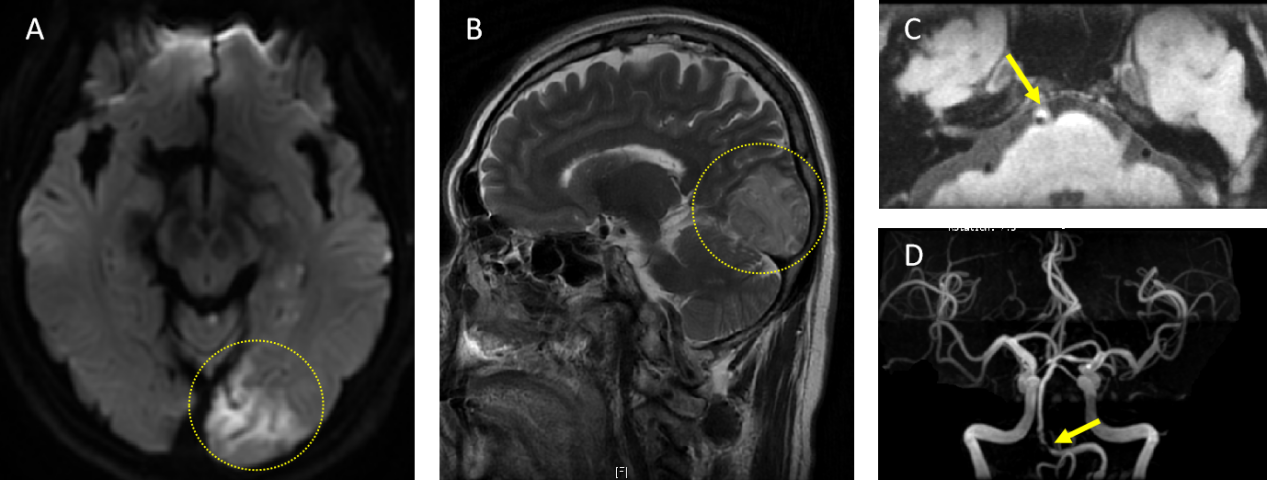

图1:A. 头颅核磁平扫DWI序列轴位相可见左侧枕叶新发梗死病灶 B. 头颅核磁平扫T2-Flair序列矢状位相亦可见枕叶梗死病灶 C. 头颅MRA高分辨序列可见椎-基底动脉汇合部不稳定斑块形成 D. 头颅MRA可见椎动脉V4段—基底动脉起始段重度狭窄

时间倒回到2个月前的某个下午,老吴眼前的房子突然开始“转了”(即眩晕),同时还出现了说话不利索、右侧手脚不灵活的症状,头颅磁共振检查发现左侧枕叶脑梗死,完善脑血管评估提示左侧椎动脉V4段及基底动脉汇合部重度狭窄合并不稳定斑块(图1)。经过急性期输液支持及口服药物治疗后,老吴的这些症状基本完全缓解了,但椎-基底动脉汇合部的血管病变尚未解除,这可是一颗能够导致卒中再发的定时炸弹,我们强烈建议老吴在脑梗死病情平稳后择期处理病变血管。